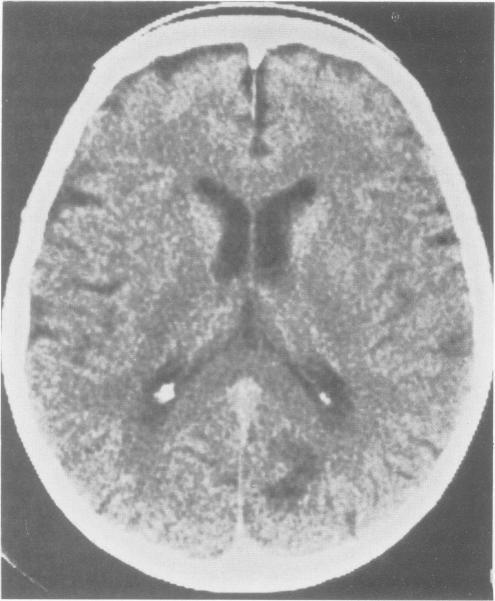

Visual hallucinations occur in diverse clinical circumstances including ophthalmologic diseases, neurologic disorders, toxic and metabolic disorders and idiopathic psychiatric illnesses. Their content, duration and timing relate to their cause and provide useful differential diagnostic information. Hallucinations must be distinguished from delusions and confabulation. A systematic approach to differentiating among hallucinatory syndromes may improve diagnostic accuracy.